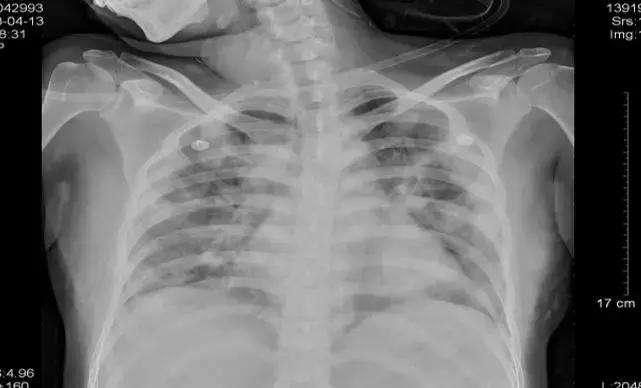

辅助检查,血常规五分类:WBC3.05*10^9/L,中性粒细胞百分比83.6%,淋巴细胞百分比11.1%。血气分析全套:PH7.467、PCO219mmHg、PO 2 58mmHg。氧合指数:276。生化,CRP104.12mg/L。胸片:双肺肺炎,如下图所示。